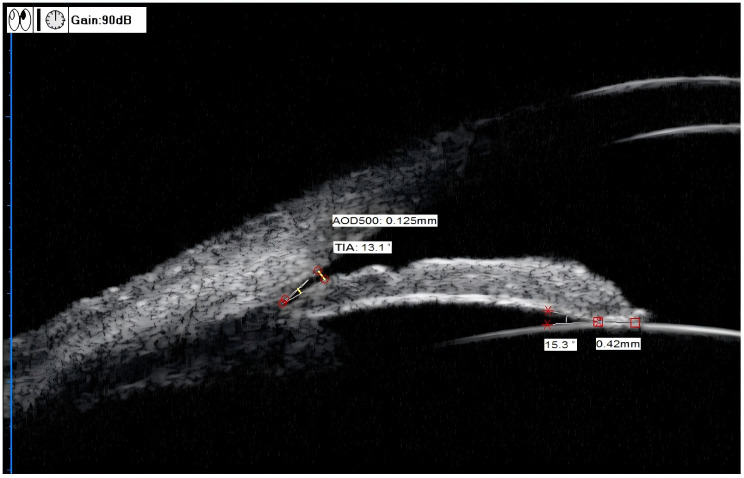

Methods: This prospective study included 82 eyes of patients with PACG, of which, 45 eyes with acute PACG (APACG), 37 with chronic PACG (CPACG). Axial length (AL) and lens thickness (LT) were measured using A-scan ultrasonography. Anterior chamber depth (ACD), pupil diameter (PD), and lens vault (LV) were measured using UBM for each group. Additionally, trabecular-iris angle (TIA), angle opening distance (AOD500), iris-lens angle (ILA), and iris-lens contact distance (ILCD) were measured in four quadrants (superior, inferior, nasal, and temporal) with UBM. The corresponding lens position (LP), relative lens position (RLP), and lens thickness/axial length factor (LAF) were calculated. Normally distributed data were compared between the two groups using an independent samples t-test. Data that did not follow a normal distribution were compared using the Mann-Whitney U test. Differences were considered statistically significant when P < 0.05, and they were considered highly statistically significant when P < 0.01.

Results: The values for angle-related parameters, including the mean TIA, TIAmax-min, mean AOD500, AOD500 max-min, and ACD, were significantly lower in the APACG group than in the CPACG group (all P < 0.05). The LP and RLP values of the APACG group were also lower than those of the CPACG group, but only the difference in LP values being statistically significant (P = 0.038). The LT, LV, LAF, mean ILCD, and ILCDmax-min values were higher than those of the CPACG group, with the differences reaching statistical significance (all P < 0.05).

Conclusion: The APACG eyes had a thicker and more-anteriorly positioned lens than those with CPACG, which results in a shallower anterior chamber and narrower anterior chamber angle. In the APACG group, the lens exhibited nonuniform laxity of the suspensory ligament across the various quadrants, poor stability, and greater susceptibility for anterior displacement or even deviation.